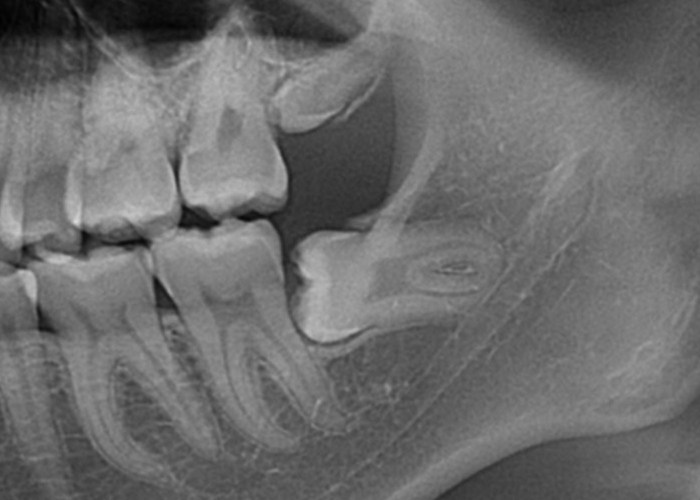

骨性完全埋伏智歯(骨に完全に埋まっている)

この場合も親知らずは通常、レントゲンやCTスキャンなどの画像検査でのみ確認できます。

完全埋伏の親知らずは、周囲の組織に直接的な問題を引き起こさない場合もありますが、将来的に問題を引き起こす可能性があります。

そのため、定期的な口腔検診や画像検査が重要です。

もしこのような歯が抜歯が必要となった場合は近隣口腔外科への紹介をする場合があります。